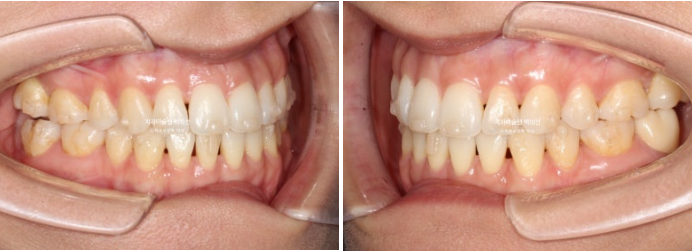

이제 전 후 비교 보겠습니다.

25.03~25.09

깔끔해진 미소가 돋보입니다.